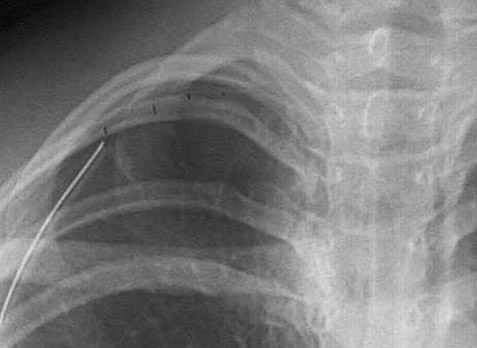

This radiograph demonstrates a pneumothorax on the right, with the faint border of the displaced visceral pleura surface is marked by the black lines. A chest tube has been inserted to re-inflate the lung.